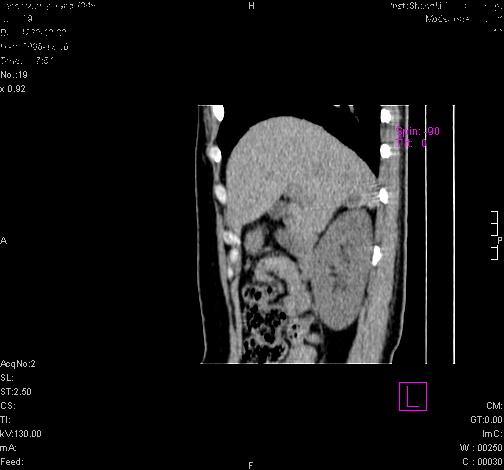

标题: CL0340:【】肾上腺囊肿,比较典型。

患者为年轻女性,查体发现右侧肾上腺囊性占位。无临床体征。

这么漂亮的图像,一看一目了然。典型的右侧肾上腺囊肿,周围有钙化。感谢搂主!

“肾上腺囊肿组织学分为4类:1)内皮细胞性,2)假性囊肿,3)寄生虫性,4)上皮细胞性。其中内皮细胞性最为常见。假性囊肿多为肾上腺内出血后遗留囊腔,囊壁无上皮细胞。寄生虫性多为包虫病引起。上皮性则很少见。”

这么明显的弧形钙化,多考虑包虫病所致的寄生虫性囊肿。

右侧肾上腺囊性密度灶囊壁有钙化。考虑肾上腺囊肿,结核?